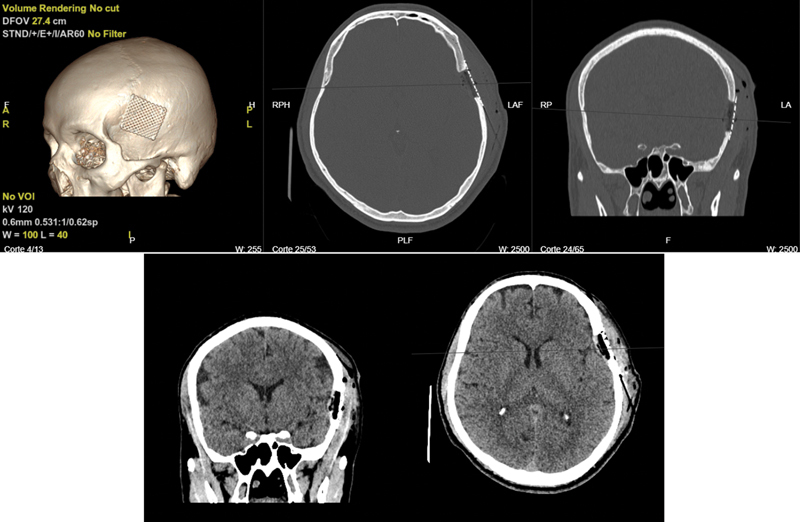

Introduction  Langerhans cell histiocytosis (LCH) is a rare proliferative systemic disease characterized by the growth of abnormal dendritic cells and wide-ranging organ involvement. This condition can affect individuals of all ages, but most commonly children, with a peak incidence in toddlers. Symptoms may vary depending on the affected organ or system. Case Report  A 43-year-old man presented with a left temporal stabbing headache unresponsive to management with therapy and nonsteroidal anti-inflammatory drugs. Initial evaluation revealed a contrast-enhanced left temporal extra-axial lesion with bone and muscle compromise. Differential diagnoses, including multiple myeloma, were explored. Initial laboratory tests and imaging studies showed no other abnormalities, except for splenomegaly and a residual granuloma in the left lung. En bloc resection of the lesion was recommended. The patient underwent surgical intervention, which included resection of the dural lesion and all borders of an infiltrating tumor within the temporalis muscle and the affected portion of the left temporal bone. Posterior pathological examination revealed LCH. Postoperative course was uneventful. Follow-up appointments were scheduled after pathology results confirmed the diagnosis. Patient has continued follow-up for the following 3 months after the surgical procedure. Further evaluations are pending. Discussion  This case report corresponds to a patient with LCH. These patients are individualized and stratified based on local or systemic involvement to determine the most appropriate type of management. This is a rare case as LCH is rare in older patients and the initial presented lesion initially mimicked a meningioma; however, its atypical behavior and associated lytic compromise led to consideration of possible differential diagnoses. Conclusion  LCH can present with lytic bone lesions, mimicking other conditions, including infiltrative neoplastic lesions. Early diagnosis and appropriate surgical management are essential for optimal patient outcomes. Long-term follow-up is crucial to monitor disease progression and response to treatment.

Abstract Image